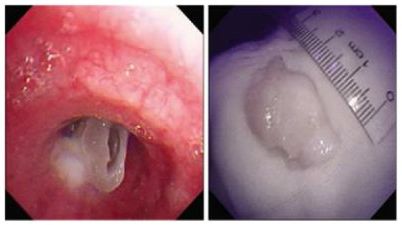

支气管镜经口进入气管。镜下见左侧主支气管近端有一白色不规则异物嵌顿于管腔,管腔大部分堵塞,周围粘膜略肿胀。在使用异物钳小心松动异物后未见明显出血,谢国钢医师随即用异物钳夹住异物沿气道去除,取出异物后支气管镜再次进入气道观察无明显出血,远端管腔通畅,未见残留异物。整个过程历时约3分钟即告完成。异物取出后患者咳嗽、呼吸困难及胸痛症状立即消失,指末氧氧饱和度升至99%。(通讯员 / 呼吸科 谢国钢 鲍鲁红)